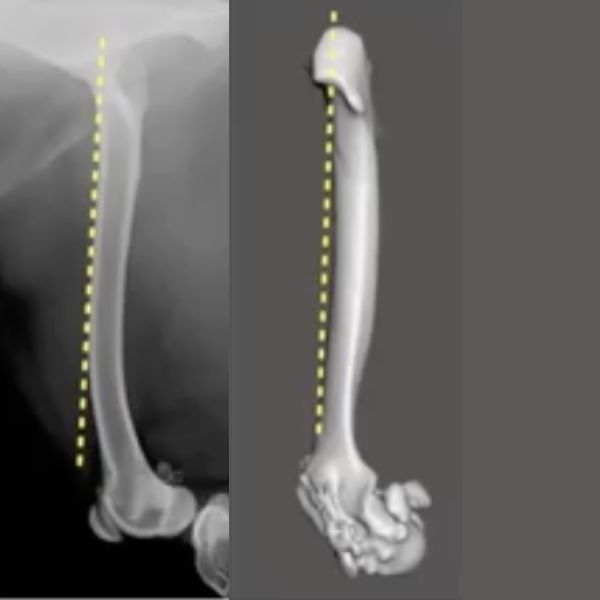

Why is this important? When we take a well-positioned, true lateral radiograph, you can get a visual impression of the anteversion angle. (Fig 11, 13:43) The image on the left is at the top end of normal, and as a rule of thumb, in a perfectly positioned lateral x-ray of the femur (whereby the femoral condyles are overlapping) about 50% of the femoral head would be cranial to the dotted yellow line that marks the cranial edge of the femur. On the right image there is no femoral head visible as it is obscured by the greater trochanter. The condyles in this image are superimposed so this confirms that the X-ray or in this case CT rendering is a true lateral. This apparent absence of any of the femoral head cranial to the line that marks the cranial edge of the femur in a well-positioned lateral radiograph, gives a strong indication that the femoral head and neck have a decreased angle of anteversion or are relatively retroverted. A decreased angle of anteversion or relative or absolute retroversion is associated with medial patella luxation as in the standing dog this externally torses or supinates the femoral condyles and trochlea groove away from the sagittal plane. This can create quite significant frontal plane offset and is strongly associated with MPL.

The second indication of concern for a significant torsional or axial deformity is as soon as we look at a perfectly positioned lateral radiograph (femoral condyles superimposed), or in this case a lateral CT rendering (Fig 14, 16:04). If you can't see 50% of the femoral head cranial to a line along the cranial edge of the femur, then you need to be suspicious that there is a significant component of femoral torsional deformity.

On the left image is an increased angle of anteversion, while the rendering on the right is a decreased angle of anteversion.